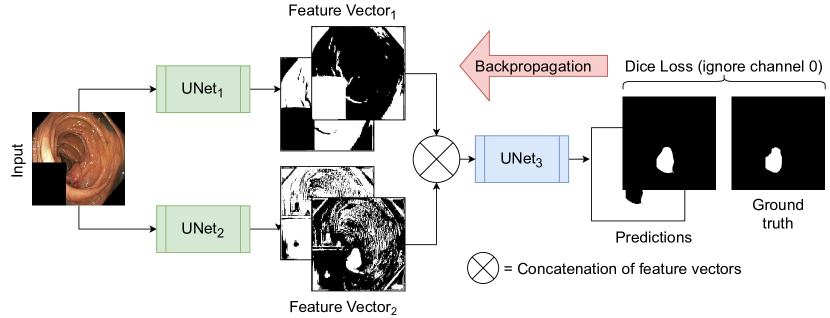

2.1 TriUNet

TriUNet is a convolutional neural network (CNN) architecture that utilizes multiple UNet [14] architectures arranged in a triangular structure as depicted in Figure 2. The model takes a single image as input, which is passed through two separate UNet models with different randomized weights. The output of both models is then concatenated before being passed through a third UNet model to predict the final segmentation mask. Figure 2 also shows an example of the intermediate representations provided by the two initial UNet models. The loss is calculated and back-propagated through the whole model, meaning the entire network is trained in one go. From the intermediate representations, we clearly see that the different UNets learn different interpretations of the data, which then are combined in one final output.